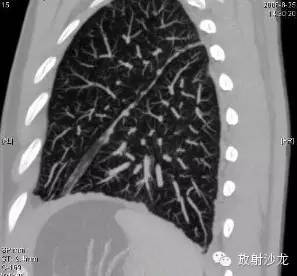

第二例:

男性47岁,因咳嗽来诊。经纵隔镜取病理及其他相关检查确诊结节病。口服激素治疗后好转(图略)。

肺门淋巴结肿大

胸膜多发小结节

右下肺小叶间隔增厚